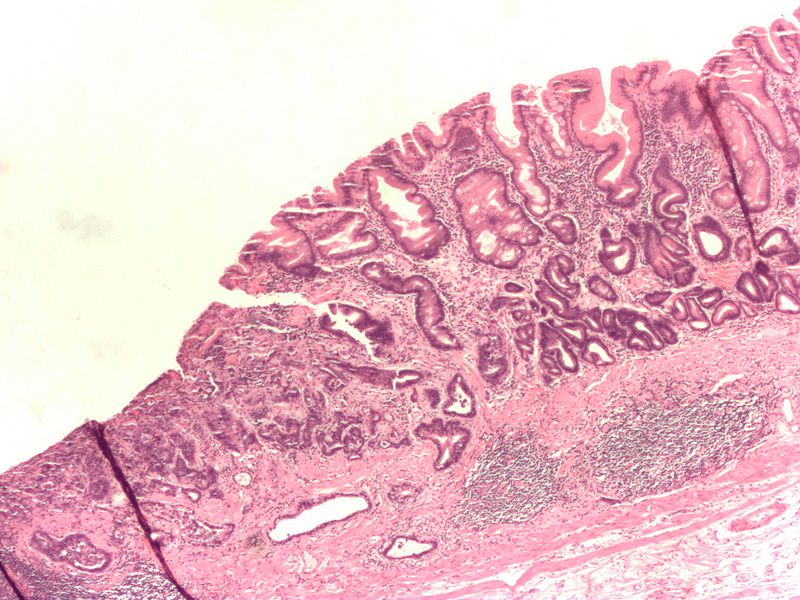

Chronic Gastritis

Chronic gastritis is due to inflammation of stomach mucosa.

Chronic gastritis is classified into two types based on underlying etiology:

- Chronic autoimmune gastritis

- Chronic H. pylori gastritis

Chronic Autoimmune Gastritis

Chronic autoimmune gastritis is the autoimmune destruction of gastric parietal cells, which are found in the stomach body and fundus.

Chronic autoimmune gastritis is linked to parietal cell and/or intrinsic factor antibodies.

Clinical features of chronic autoimmune gastritis include:

- Atrophy of mucosa with intestinal metaplasia

- Achlorhydria with antral G-cell hyperplasia and elevated gastrin levels

- Megaloblastic (pernicious) anemia because of lack of intrinsic factor

Patients with chronic autoimmune gastritis have increased risk for gastric adenocarcinoma (intestinal type).